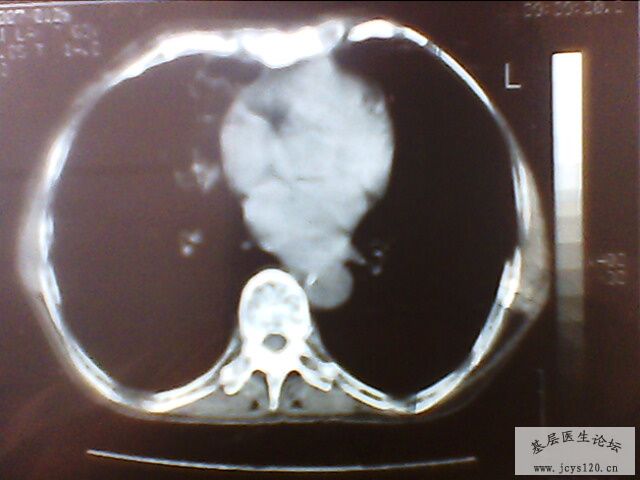

辅助检查:在县医院行肺部CT检查(附件是手机拍照的,效果不是很好,CT只拍下有意义的2个层面)

CT报告:右肺中叶病变,考虑炎症可能性大,建议治疗后复查